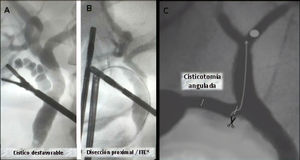

Nueva disección del conducto císticoLa disección adecuada del conducto cístico es aquella con la que logramos la visión crítica de seguridad, sin embargo en císticos desfavorables (cuando tiene un trayecto tortuoso o presenta litiasis cística7,8) es difícil realizar la colangiografía intraoperatoria, y más aún una instrumentación transcística.

En estos casos es necesaria una nueva disección del conducto más próximo a la vía biliar principal, permitiendo rectificar el trayecto, realizar una nueva cisticotomía y facilitar su canalización e instrumentación posterior (figs. 4A y 4B).

Cisticotomía angulada o coledocotomía mínimaLa presencia de cálculos intrahepáticos es infrecuente, y más aún lo es la imposibilidad de descenderlos por debajo de la unión cístico coledociana. Ante esta excepcional situación realizamos una nueva cisticotomía en la cara inferior, próxima a la unión, que nos permite direccionar la canastilla hacia la vía biliar intrahepática9.

En algunos casos el cierre de la misma debe ser realizado con puntos debido a la proximidad con la vía biliar principal (fig. 4C).